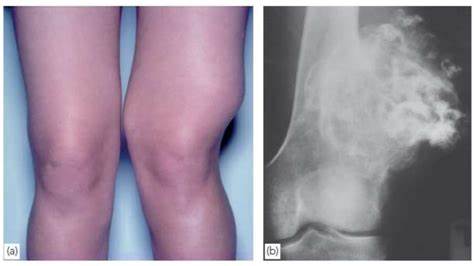

(1) 거대세포종 (Giant cell tumor)